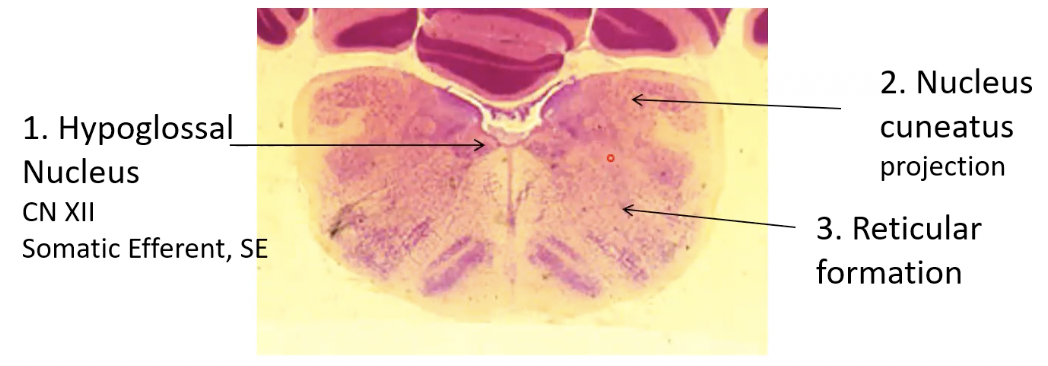

12?

A

hypoglossal

somatic motor

__ regulates cardiovascular system control , respiratory control, pain sensitivity control, alertness, awareness, and consciousness.

reticular formation (in the brain stem)

reticular formation → arousal, respiratory, cardiac, vasomotor, gastric network